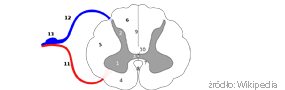

Rdzeń kręgowy u człowieka jest tworem grubości palca zbudowanym z tkanki nerwowej i otoczony przez kręgosłup. Rdzeń kręgowy otrzymuje bodźce nerwowe ze skóry, mięśni, więzadeł i innych tkanek organizmu.

Rdzeń kręgowy przesyła informacje w postaci elektrycznych impulsów do mózgu, poprzez miliony włókien nerwowych zgrupowanych razem w wiązkach. Impulsy, które regulują aktywność ruchowa, są generowane w mózgu i wysyłane do rdzenia kręgowego poprzez szybko przewodzące włókna nerwowe, które kończą się w lokalnych rdzeniowych obwodach motorycznych. Stad elektryczne impulsy, które bezpośrednio koordynują skurcz mięśni, docierają do poszczególnych włókien mięśniowych poprzez nerwy obwodowe. Uderzenie w kręgosłup może powodować zwichniecie poszczególnych kręgów i poważne uszkodzenie rdzenia kręgowego, włącznie z całkowitym wyłączeniem jego funkcji.

Tworzą się zbiorniki (cysty) wypełnione płynem, otoczone zabliźniona tkanka. Czy reakcja zapalna prowadzi do dodatkowego powiększenia uszkodzenia tkanek rdzenia kręgowego, jest sprawa nie w pełni wyjaśniona i dyskusyjna. Warto zauważyć, ze obrazy uszkodzonych rdzeni kręgowych u pacjentów z paraliżem nóg bądź wszystkich kończyn pokazują, ze całkowite anatomiczne przerwanie rdzenia kręgowego jest bardzo rzadkie. Stwierdza się natomiast w tych przypadkach przetrwale „mosty” zbudowane z tkanki nerwowej łączące miejsca poniżej i powyżej uszkodzenia, zwłaszcza na obrzeżach rdzenia kręgowego.